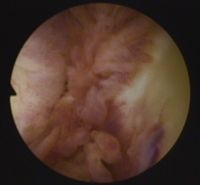

Arthroskopische Sicht auf einen entzündeten Schleimbeutel im Hüftgelenk. © Gelenk-Klinik